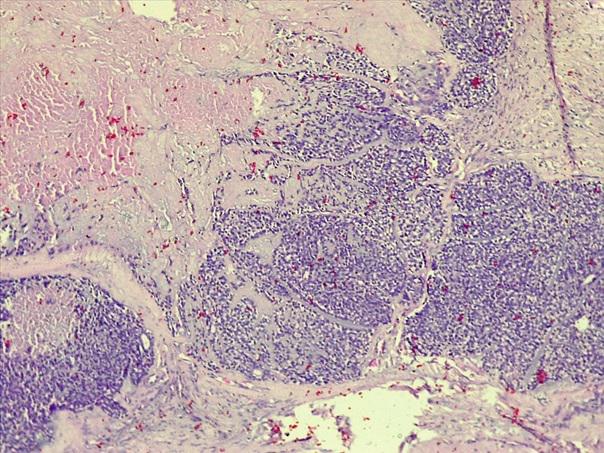

*Case 2 : Dr Rimamskep Ifusumu/ Prof Modupeola Samaila

email: mamak97@yahoo.com

Clinical details: Female, 38years, Ovarian mass ?